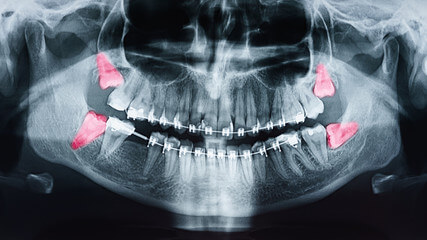

때때로 사랑니가 뼈에 묻혀서 그 주위에 낭종과 같은 것을 일으켜 뼈를 손상시키기 때문에 사랑니를 발치하는 경우가 많습니다. 그러나 사랑니는 뼈가 잘 발달되어 있고 잇몸으로 덮여 있지 않다면 발치 할 필요가 없다고 합니다.

사랑니가 제 역할을 할 만큼 잘 나오고 있는지, 주변 치아나 잇몸, 뼈에 해를 끼칠 수 있는지 판단하는 것보다 전문의를 찾아가는 것이 좋습니다.

드라이소켓이란?

드라이소켓은 사랑니 발치 후 제대로 치유되지 않아 붓거나 염증이 발생하면서 통증이 나타날 수 있습니다. 사랑니 발치 후의 대표적인 부작용으로는 상처 치유 과정에서 혈전이 제대로 형성되지 않거나, 형성되더라도 3일 이내에 제거되어 사랑니 아래 잇몸뼈가 그대로 노출됩니다.

잇몸이 노출되면 입안에 남아있던 세균이 침투해 염증을 일으켜 심한 통증을 유발할 수 있습니다. 또한 잇몸의 경우 다른 신체 조직과 달리 딱지가 한번 빠지면 다시 형성되기 어려우므로 사랑니 발치 후 드라이소켓이 의심된다면 빠른 시일 내에 치과에서 봉합하는 것이 필요합니다.